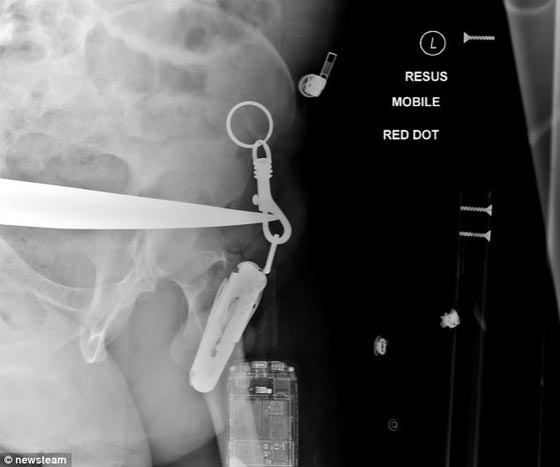

أنقذت العناية الإلهية مزارعاً بريطانياً من موت محتم، بعد أن اخترقت شفرة حصادة زراعية بطول (46 سم) جذعه السفلي، قبل أن تخرج من الجهة الأخرى وتعلق بحلقة سلسلة المفاتيح التي كانت في "جيب بنطلونه". ووفقاً لصحيفة الـ "دايلي ميل" فقد أظهرت الأشعة السينية التي التقطت في المشفى، كم كان جراهام هيتلي (52 عاماً) محظوظاً بسلامة أعضائه الحيوية الهامة، نظراً لضخامة الشفرة المعدنية التي اخترقت جسده.

وأضافت أن الحادثة وقعت بسبب خطأ المزارع نفسه، حيث نسي ربط مكابح الحصادة بعد انتهائه من العمل عليها، لتتهاوى الآلية التي تزن نحو 1.5 طن، نحوه وتخترق إحدى شفرات البكرة الأمامية أعلى ردفه الأيمن متجاوزة أحشاءه حتى خروجها من الجزء السفلي الأيسر لبطنه. وقالت السلطات إن جراهام كان محظوظاً بعد سماع جيرانه صرخات الاستغاثة التي أطلقها، حيث عجز عن تحرير نفسه، ليتم إسعافه جواً، وأضافت أنه ترك المستشفى في غضون ستة أيام من إخراج الشفرة من جذعه.